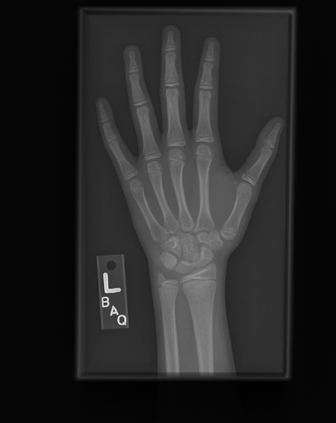

Deep neural networks are increasingly being used for the analysis of medical images. However, most works neglect the uncertainty in the model's prediction. We propose an uncertainty-aware deep kernel learning model which permits the estimation of the uncertainty in the prediction by a pipeline of a Convolutional Neural Network and a sparse Gaussian Process. Furthermore, we adapt different pre-training methods to investigate their impacts on the proposed model. We apply our approach to Bone Age Prediction and Lesion Localization. In most cases, the proposed model shows better performance compared to common architectures. More importantly, our model expresses systematically higher confidence in more accurate predictions and less confidence in less accurate ones. Our model can also be used to detect challenging and controversial test samples. Compared to related methods such as Monte-Carlo Dropout, our approach derives the uncertainty information in a purely analytical fashion and is thus computationally more efficient.